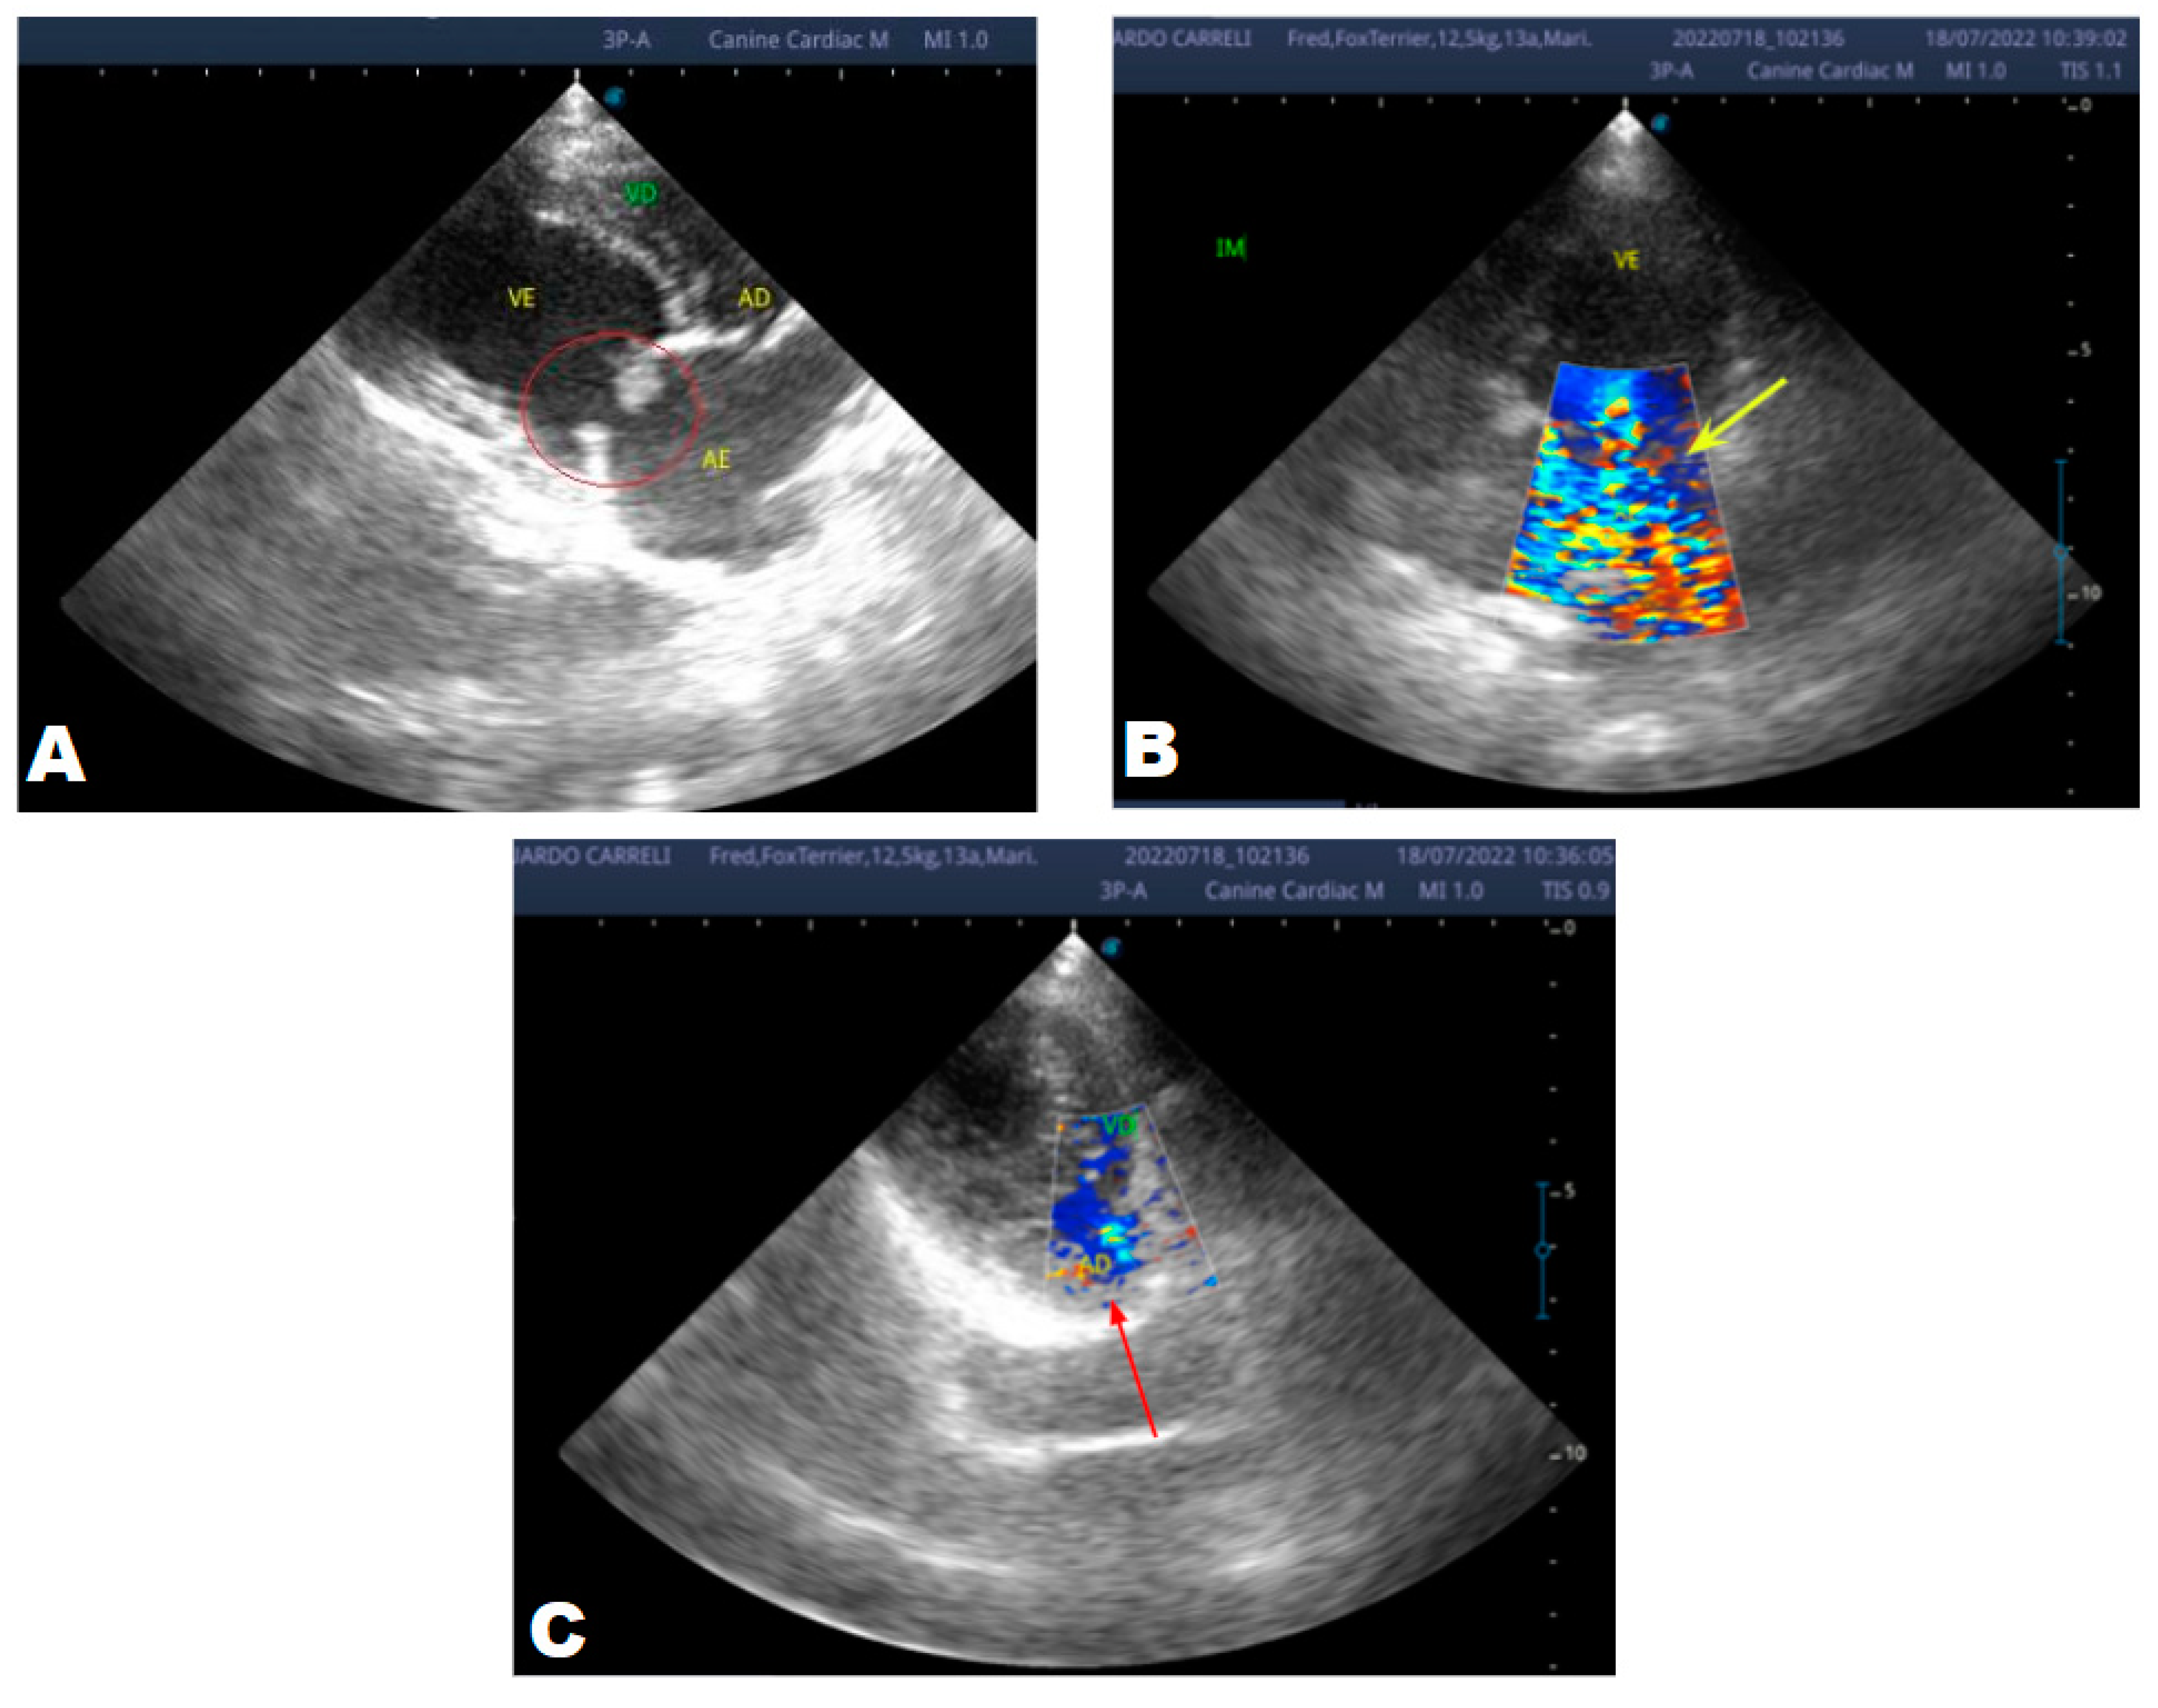

In the anamnesis, the owners reported that the animal never had coughs, syncope, or convulsions, just tremors since it was a puppy. On physical examination, a grade 3/6 murmur was heard in the mitral focus, normal heart and respiratory rates and systemic arterial hypertension (180mmHg), and normal-colored mucous membranes. An echocardiogram (ECHO) was performed (Figure 1), which showed a thickened mitral valve and enlarged heart chambers. At first was prescribed Pimobendan PO at a dose of 0.25 mg/kg BID, continuous use, and requested to return in 30 days.

In the reported case, the patient arrived at the clinic in stage B2, where he was asymptomatic and the echocardiographic examination showed enlargement of the left heart chambers, thickened and degenerated mitral valve (Figure 1), left ventricular diastolic dimension above normal limits. , with normal systolic function parameters, characterizing systolic dysfunction. The thickening and degeneration of the mitral valve indicates its insufficiency and the other changes characterize diastolic dysfunction.

Figure 1. Echocardiogram 2021: Thickened/degenerated mitral valve (A); Observed in Doppler mode, significant mitral valve insufficiency (B); Hemodynamic assessment - Mitral regurgitation gradient: 3.45 m/s / 47.68 mmHg; enlargement of left cardiac chambers; left ventricular diastolic dimension above normal limits was observed.